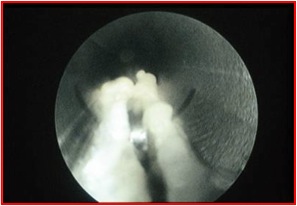

While improvements in the understanding of plantar fasciopathy and advances in diagnosis and treatment have reduced the need for endoscopic plantar fasciotomy (EPF), it remains an efficacious procedure for properly selected patients.

Endoscopic plantar fasciotomy (EPF) emerged in the literature in 1991 and has remained an efficacious, minimally invasive technique to this day.1-6 There is no doubt that EPF is still a viable and efficacious procedure. What has changed is our understanding of plantar fasciopathy and that has forced a paradigm shift in the treatment of plantar fasciopathy, which has given EPF a different space in that paradigm.

The fact of the matter is that while the surgical technique of EPF has been a mainstay in the treatment of severe plantar fasciopathy and is probably one of the most peer-reviewed surgical techniques in the podiatric surgical armamentarium, the understanding of the condition that surgeons developed the modality to treat has radically changed for the better.

Nevertheless, EPF is highly efficacious, minimally invasive and safe. The long-term efficacy of EPF is well established.16 Additionally, patients reportedly have fewer complications with EPF in comparison to open heel surgery or even ESWT.4 As with any surgery, complications can occur and this is no different with EPF. Most complications with EPF are due to excessive activity in the postoperative period before the fascia has had enough time to heal. Close monitoring by the surgeon can mitigate this factor. I usually recommend no more than five minutes of standing or walking per hour for the first four weeks without a walking boot, and minimizing ambulation as much as possible during the first two weeks after EPF. I cannot emphasize enough the avoidance of performing bilateral surgery.